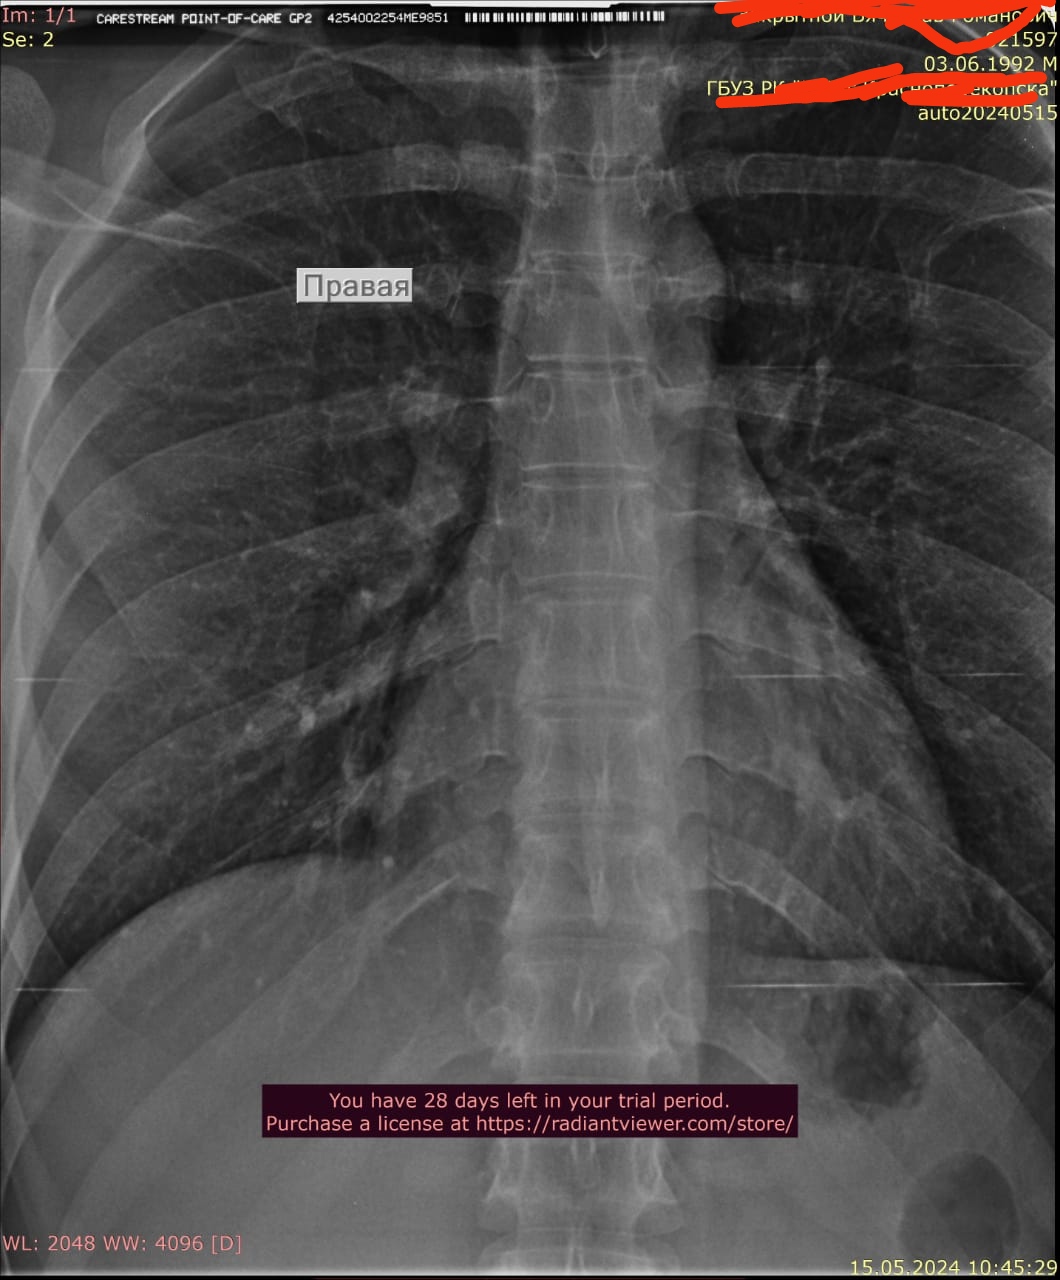

Что такое малоконтрастная рентгенограмма органов грудной клетки